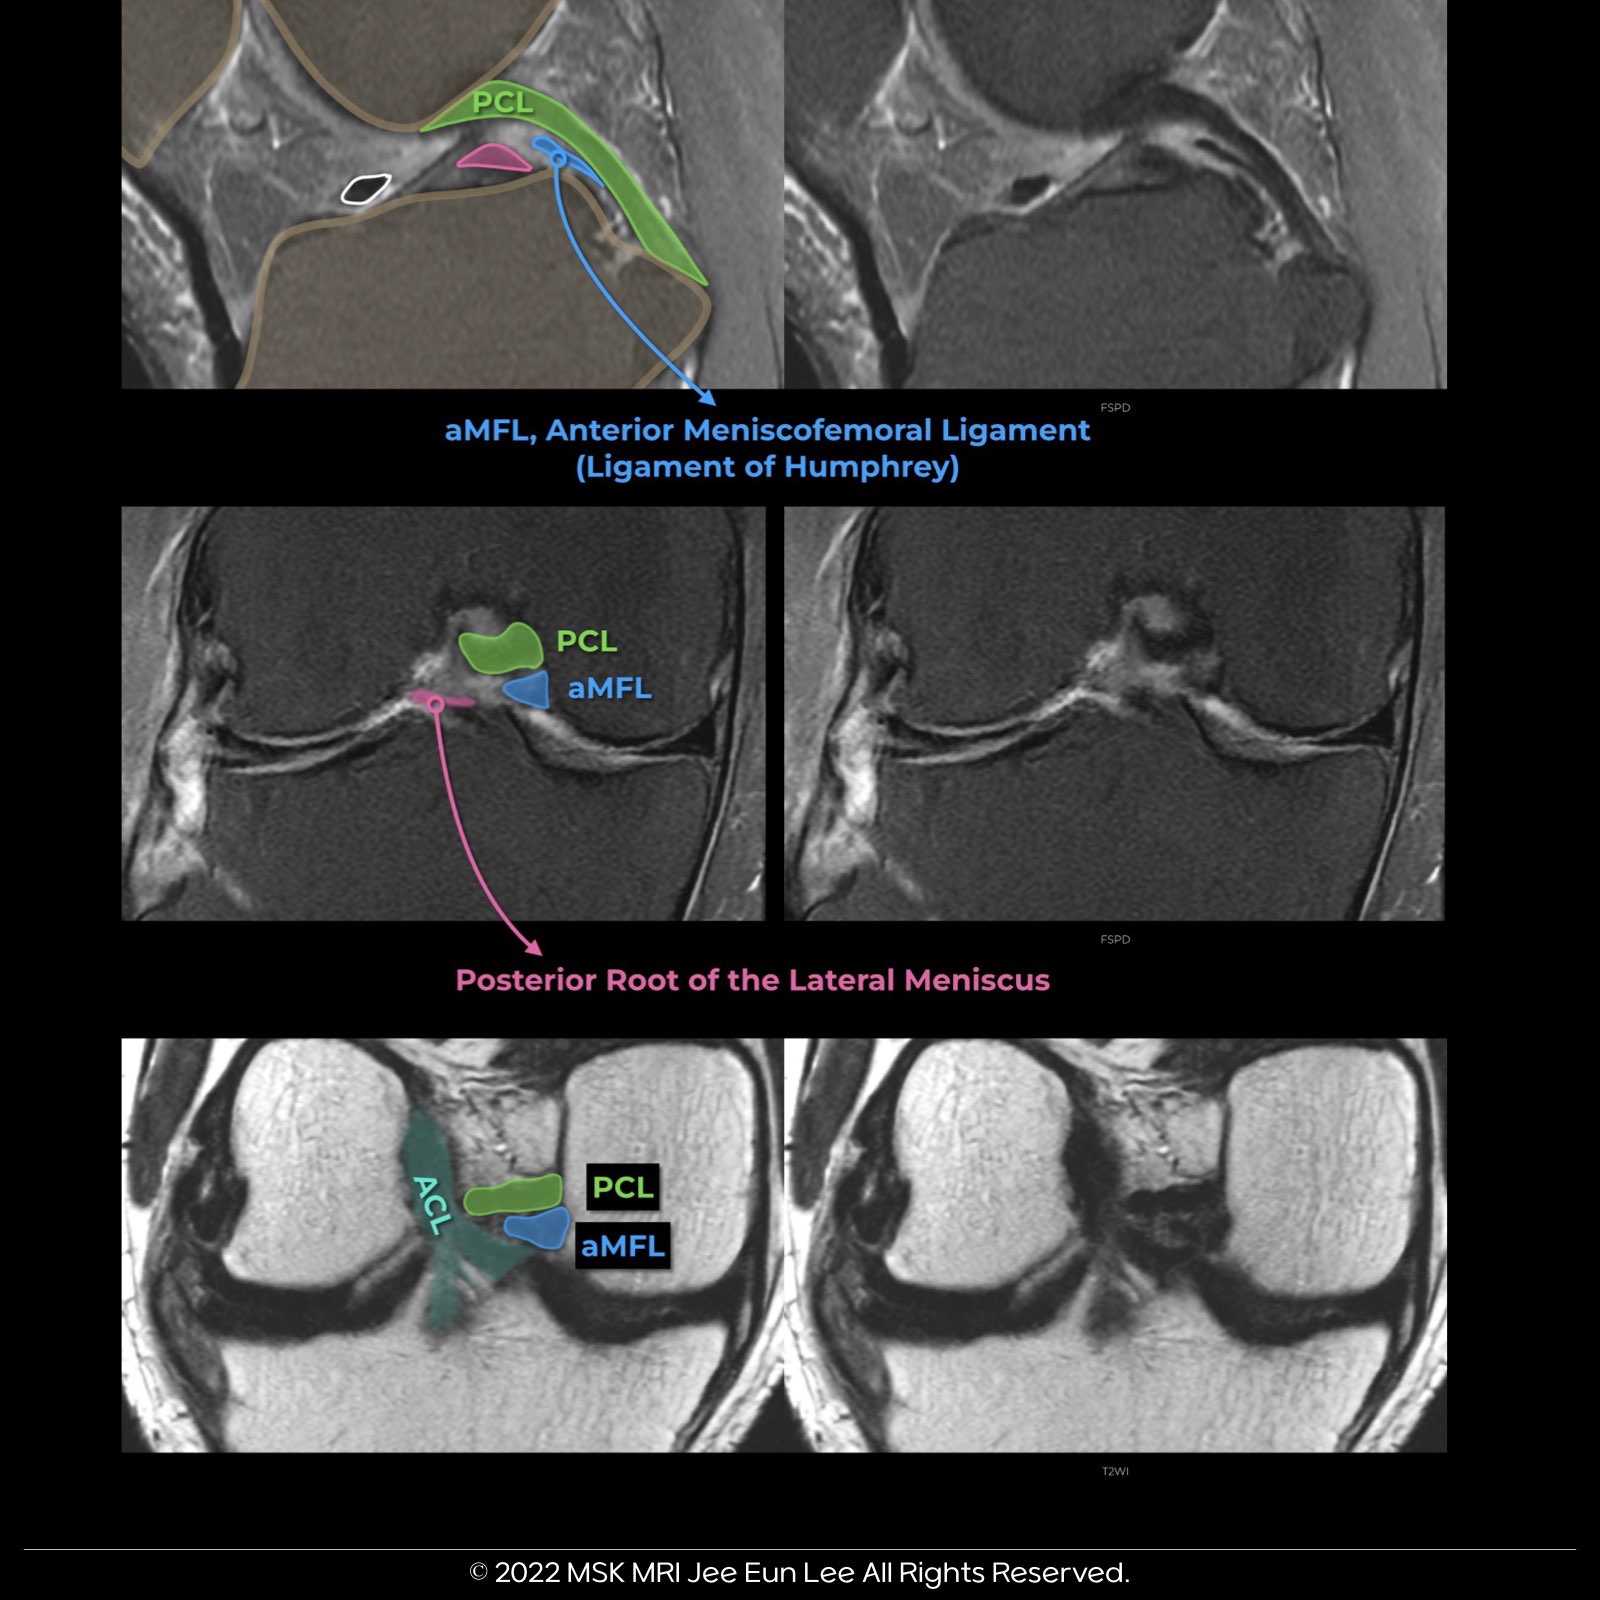

1๏ธโฃ The aMFL (anterior MFL), also known as the Ligament of Humphrey, originates on the Medial Femoral Condyle and is typically found distal to the PMB of the PCL.

โจ The MFL, a critical component of the knee, originates from the posterior horn of the lateral meniscus and inserts onto the lateral aspect of the posterior medial femoral condyle. It plays a key role in the stability and function of the knee joint.